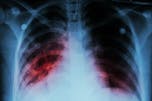

Cada año matas a más de 1,6 millones de personas y te transmites a más de 10 millones, y ya sumas un total de 2.000 millones de personas contagiadas, ¡que es la cuarta parte del mundo! Es un gran logro para alguien que apenas mide dos milésimas de milímetro. ¿Cómo te sientes? ¿Estás orgullosa, estás contenta? En cualquier caso, estás acabada.